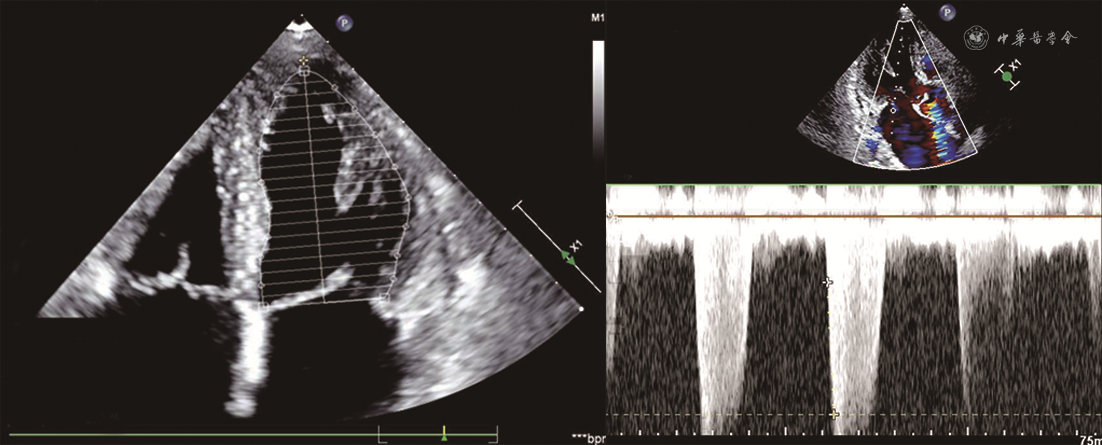

患者男,68岁,主因“胸痛、后背痛1 d”于2019年12月25日入院。患者有支气管哮喘病史,长期口服孟鲁司特。否认系统病史,否认食物、药物过敏史。无疫水、疫区接触史,无寄生虫接触史。入院体格检查:体温36.2 ℃,脉搏71次/min,呼吸25次/min,血压85/45 mmHg(1 mmHg=0.133 kPa)。神清语利,查体合作。浅表淋巴结未触及肿大。双肺呼吸音粗,可闻及肺底湿性啰音。心脏律齐,各瓣膜未闻及明显病理性杂音。腹软,无压痛及反跳痛。双下肢无水肿。血常规:白细胞计数22.39×109/L,嗜酸性粒细胞绝对值16.71×109/L[参考值(0.05~0.50)×109/L]。血浆D-二聚体1 027 μg/L(参考值<500 μg/L),肌钙蛋白T 2.950 μg/L,N末端B型利钠肽原9 949 ng/L(参考值0~1 800 ng/L),C反应蛋白1.32 mg/dl,免疫球蛋白E 421 IU/ml。心电图:窦律,完全性右束支传导阻滞。超声心动图:左心室舒张末期内径(LVEDD)58 mm,左心室收缩末期内径(LVESD)42 mm,左心房前后径43 mm,右心房左右径44 mm,左心室壁节段性运动异常,二尖瓣、三尖瓣中重度反流,下腔静脉内径增宽,左心室射血分数(LVEF)为43%,肺动脉收缩压70 mmHg(图1)。冠状动脉CT血管造影(CTA):冠状动脉呈右优势型,左、右冠状动脉未见有意义狭窄。给予补液、多巴胺、甲基泼尼龙静脉滴注以及口服甲泼尼龙等对症治疗,血压可维持在90/60 mmHg左右。2020年1月5日复查超声心动图:下腔静脉增宽,左心室壁运动普遍减弱,左心室收缩、舒张功能下降,二尖瓣轻度反流,主动脉瓣、三尖瓣轻度反流,心包积液(少量),肺动脉收缩压45 mmHg。骨髓(胸骨、髂骨)细胞学检查:粒细胞系统、红细胞系统、巨细胞系统三系增生,骨髓嗜酸性粒细胞增多。骨髓病理:骨髓增生低下,粒细胞与红细胞比例略增高,偏成熟为主,巨核细胞数量正常,形态未见特殊,可见散在嗜酸性粒细胞,稍多。基因检查报告:未检测到FIP1L1/PDGFRα融合基因,未检测到PDGFRβ、PGFR1、TEL-ABL1基因重排,未检测到JAK2基因分离重排。患者症状好转,生命体征平稳出院。出院诊断:特发性嗜酸性粒细胞增多症,Löeffler心内膜炎,心律失常(完全性右束支传导阻滞),纽约心脏协会(NYHA)心功能Ⅱ级、肺动脉高压、支气管哮喘。出院后口服甲泼尼龙片半年。出院后5个月随访,患者血常规正常,2020年5月28日复查超声心动图示LVEDD 57 mm、LVESD 42 mm、左心房前后径35 mm、右心房左右径41 mm、左心室壁节段性运动异常、二尖瓣和三尖瓣轻中度反流、LVEF为54%、肺动脉收缩压30 mmHg(图2)。2020年6月12日完善心脏磁共振检查,可见心脏饱满,左心室游离壁心肌变薄,以乳头肌至心尖水平外侧壁为著,右心室心肌形态未见明确异常,左、右心室收缩及舒张功能未见明确异常。钆对比剂延迟强化(LGE)见左心室心内膜区多发斑点状,二尖瓣、三尖瓣未见明显反流信号,提示左心室心肌弥漫性损伤,符合Löeffler心内膜炎表现(图3)。考虑心脏重构有加重趋势,除继续给予口服甲泼尼龙片外,加用沙库巴曲缬沙坦(ARNI)抑制心脏重构。出院后9个月(2020年9月21日)再次复查超声心动图(图4):LVEDD 50 mm,LVESD 35 mm,左心房前后径34 mm,右心房左右径37 mm,左心室壁节段性运动异常,二尖瓣、三尖瓣轻度反流,LVEF 56%,肺动脉收缩压30 mmHg。